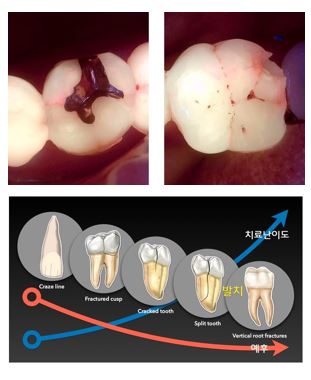

[민치과의웜] 치아균열(크랙치아)에 대한 진단과 치료

요즘들어 치아의 잔금이나 균열, 심한 경우 치아 파절로

저희 병원에 방문하는 분들이 부쩍 늘었습니다.

이 중 가장 큰 통증을 일으키는 것은 치아에 발생한 크랙(CRACK)입니다.

크랙 치아에 대한 치료 지침이 있어 안내드립니다.

저희 치과는 크랙에 대한 더욱 정확한 진단을 위해 큐레이 장비를 도입하여 사용 중입니다.